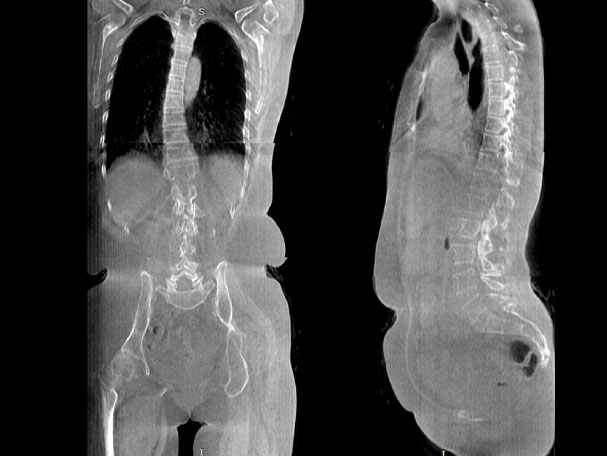

填补常规CT/MR空白

助力术前规划和术后评估

腰椎

VR体绘制重建